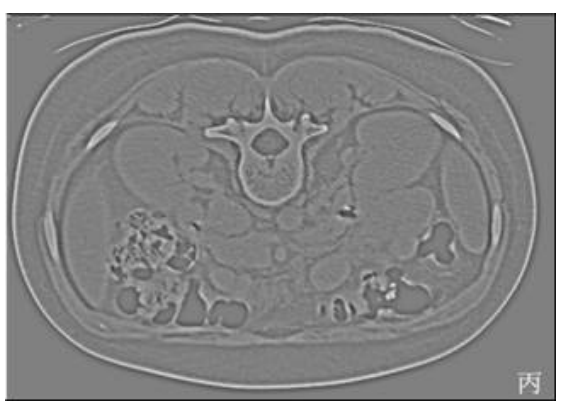

25.附圖中,甲為原始影像,影像乙與影像丙最有可能為何種影像濾波處理後的結果?

(A)影像乙為高通(high-pass)濾波而影像丙為低通(low-pass)濾波 (B)影像乙為低通(low-pass)濾波而影像丙為高通(high-pass)濾波 (C)二者皆為高通(high-pass)濾波但使用不同之kernel (D)二者皆為低通(low-pass)濾波但使用不同之kernel